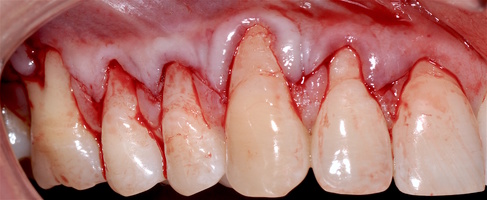

В области от 1.6 до 2.6 и от 3.6 до 4.6 все зубы имеют некариозные поражения разной степени, такие как эрозии эмали и клиновидные дефекты, вовлекающие в процесс ткани эмали и дентина. Подвижности зубов не выявлено (рис. 1а-е) [9].

При анализе и описании компьютерной конусно-лучевой томографии (рис. 2а-г) была выявлена генерализованная первичная дегисценция вестибулярной пластинки кости от 1/2 до 3/4 длины корней зубов, зубной ряд целостный, все зубы витальны, кариозных поражений нет. Тип кости 1-2 (Lechkolm и Zarb, 1983), первичная дегисценция вестибулярной костной пластинки превышает пределы возрастной атрофии.

Исходный диагноз: генерализованные рецессии десны 1 и 2 класса по Миллеру [7, 9, 10].